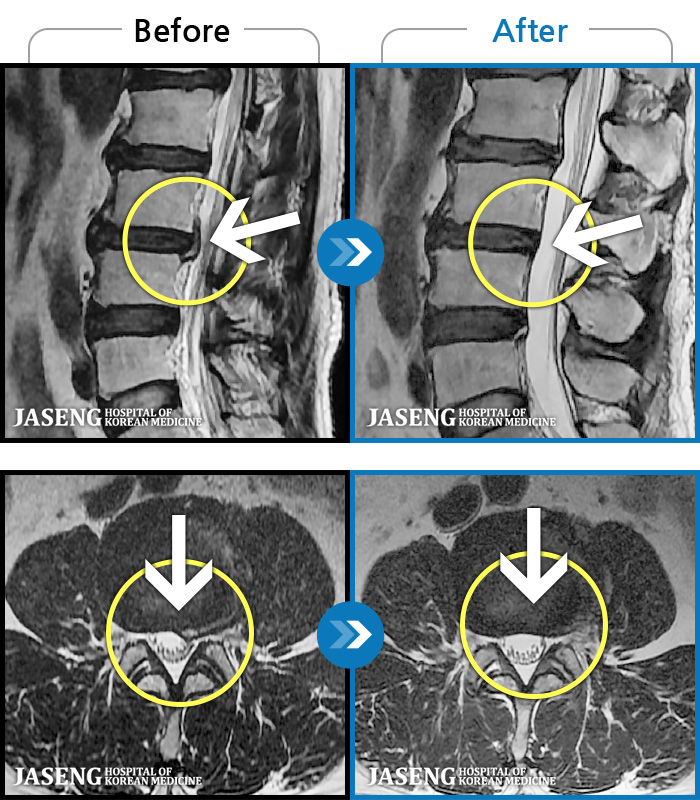

MRI 치료사례

허리디스크

해운대 · 김상돈 원장

허리가 찌릿찌릿하고 찢어질 것 같은 통증

촬영시기

2024.01.08 ~ 2025.08.12

2025.08.29